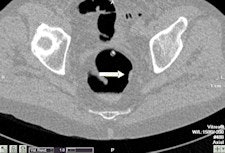

In a study published online March 11 by the European Journal of Radiology, five radiographers underwent a teletraining program on CTC based on interpretation of 75 cases. The group had no experience with CTC and only very basic knowledge of colonic anatomy and pathology, although they had practical experience of abdominal CT and barium enema procedures (EJR, March 11, 2011).

After initial training, good sensitivity and positive predictive value (PPV) were obtained for polyps with a diameter of more than 6 mm, according to lead author Carsten Lauridsen, from the department of radiography education at Copenhagen's Metropolitan University College. In the training cases, overall per-polyp sensitivity was between 57% and 69.1%. Overall per-patient sensitivity, specificity, and PPV sensitivity was between 78.3% and 86.4%. In the test cases, overall per-polyp sensitivity was between 80.7% and 94.7%, and overall per-patient sensitivity, specificity, and PPV were between 64% and 92.9%.